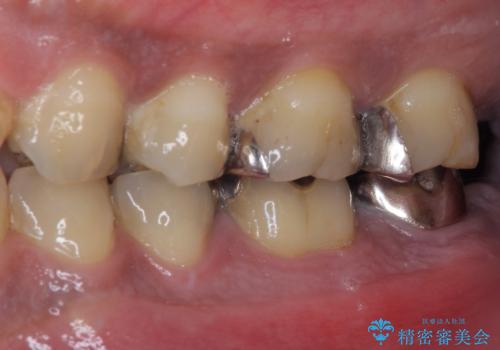

- 食事などで噛んだ時に奥歯が痛むとのことで来院された患者様です。

レントゲン写真より、一番奥の歯の根尖部に大きな病変(炎症により骨が溶けている状態)が認められたため、根管治療を行うこととしました。

根管治療後に痛みは一次消退しましたが、半年ほど経過しても病変は改善しておらず、歯根が破折している状態となっていました。

歯根が破折した歯は抜歯となるため、抜歯して病変の部分に骨が回復するのを待って、インプラントによる補綴治療を行うこととしました。